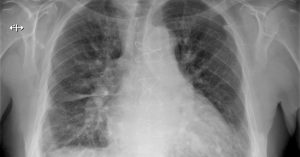

Ho gà ở trẻ sơ sinh (Pertusis) là một bệnh lý nhiễm trùng – nhiễm độc cấp tính đường hô hấp. Bệnh gây ra bởi vi khuẩn Bordetella pertussis. Triệu chứng thường gặp là các cơn ho dữ dội, mất kiểm soát, có thể dẫn tới khó thở, âm thanh thở rít. Ba mẹ thường […]